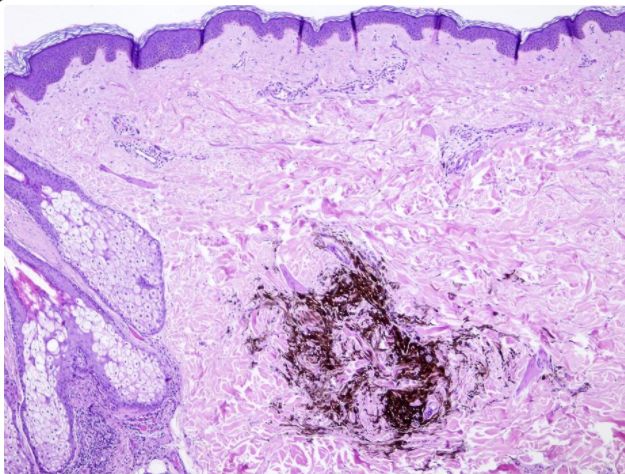

_____ nevus is a non-nested dermal infiltration of highly dendritic heavily pigmented nevus cells